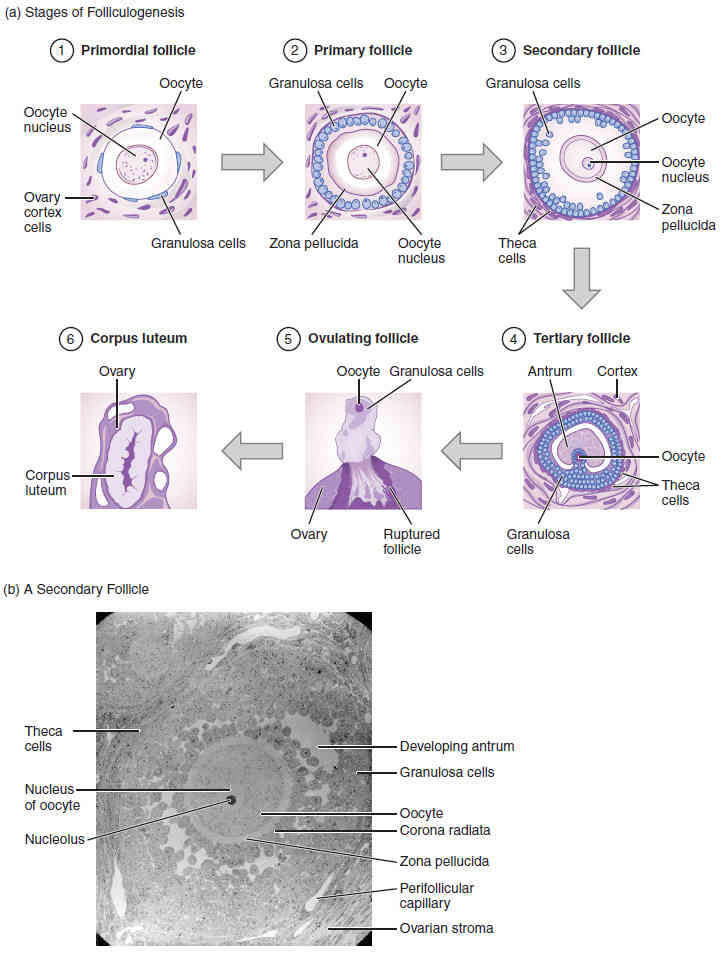

This page is under construction. For now, it is just a resource of the images found in the OpenStax Anatomy and Physiology Handbook. It wil slowly change into a revision tool. Each slide has a number. Use this to refer to the slide. When completed, it will have an unlabelled section, with labelled slides in parallel. On the unlabelled slides, write your answer and use the labelled slide to assess yourself. Keep track by also noting the number on each slide. Improvement at each attempt is important, more so than full marks on a first attempt.